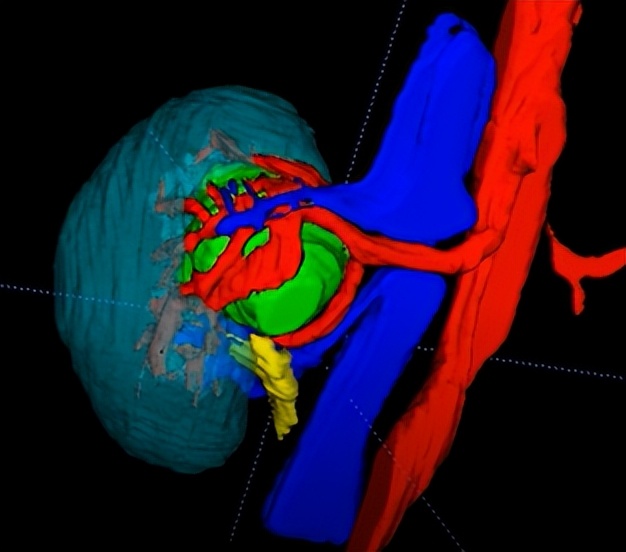

在手术前,朱绍兴教授团队利用3D成像技术,将CT影像二维数据在计算机上进行三维重建,将肾脏血管、集合系统与肿瘤的空间关系做了多角度的直观显示,进而制定了详实的手术计划和预案。

▲图1:术前肾脏CT影像及三维重建图,可见肿瘤嵌入肾门中央,被肾脏大血管所包绕(红色箭头所指处为肾肿瘤,三维重建图中绿色部分为肾肿瘤、红色部分肾动脉、蓝色部分为肾静脉、青色部分为肾脏、黄色为输尿管肾盂)

“以前就算开刀进入肾脏内部,也无法看得这么清楚。现在通过三维重建技术,医生在术前就能准确地评估病变周围情况,依此模拟手术场景、规划手术路径,为最大限度地在切除肿瘤的同时,保留肾内大血管和其他重要结构且最大程度地保留肾单位奠定基础。” 02 精确定位肿瘤:腔内超声“透视眼”助力精准定位肿瘤